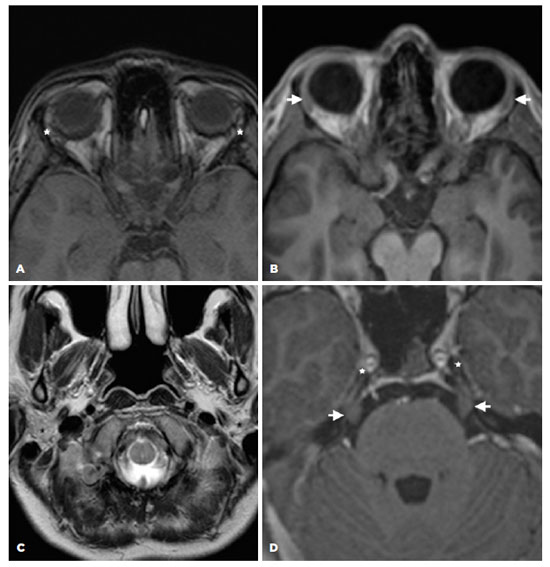

A 32-year-old white man presented with DES and dry mouth for 18 months. Prior to the visit, he received hydroxychloroquine sulfate, corticosteroids, topical cyclosporine, eyedrops, and punctual occlusion for presumed DES secondary to SS, without improvement. His only remarkable previous history was the use of AAS for bodybuilding, as follows: durateston (a solution of four molecules of synthetic testosterone, composed of propionate, fempropionate, isocaproate, and decanoate of testosterone at 30, 60, 60, and 100 mg of each compound per ml, respectively) at one intramuscular injection per week; and stanzonolol (100 mg) via intramuscular injection twice a week. Both were used, as mentioned above, for eight consecutive weeks, two months before the onset of symptoms. No other medications or diseases were reported. The ophthalmological examination demonstrated a visual acuity of 1.0 OU; a TFBUT of 8 s OU; no corneal fluorescein staining; and an ST of 40 mm OU. Examinations of MG and lid margins were normal, but the tarsal conjunctiva exhibited hyperemic and conjunctiva concretions (Figure 2). The OSDI was 90%, and the whole saliva flow was 0.20 ml/min. Serological tests for autoimmune and viral systemic diseases, including anti-Ro/SSA, anti-La/SSB, anti-dsDNA, anti-SM, anti-RNP, ANA, and rheumatoid factor, in addition to blood hormonal assays, were normal. A biopsy of his minor lip SG revealed a focus score of zero. The MRI evidenced that both LGs and the parotid SGs were absent (Figure 2A and B).

11-fig02tb.jpg)